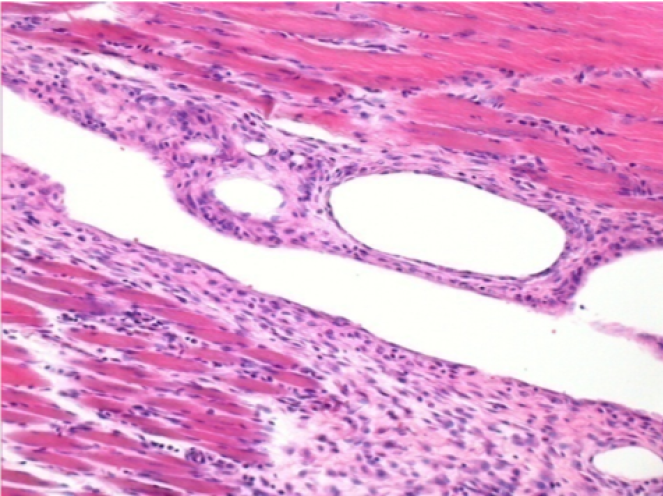

7 months (D210)after Endopeel IM Injection 0.1ml in the right pretibial muscle.

Complete Restitutio ad integrum after 7 months